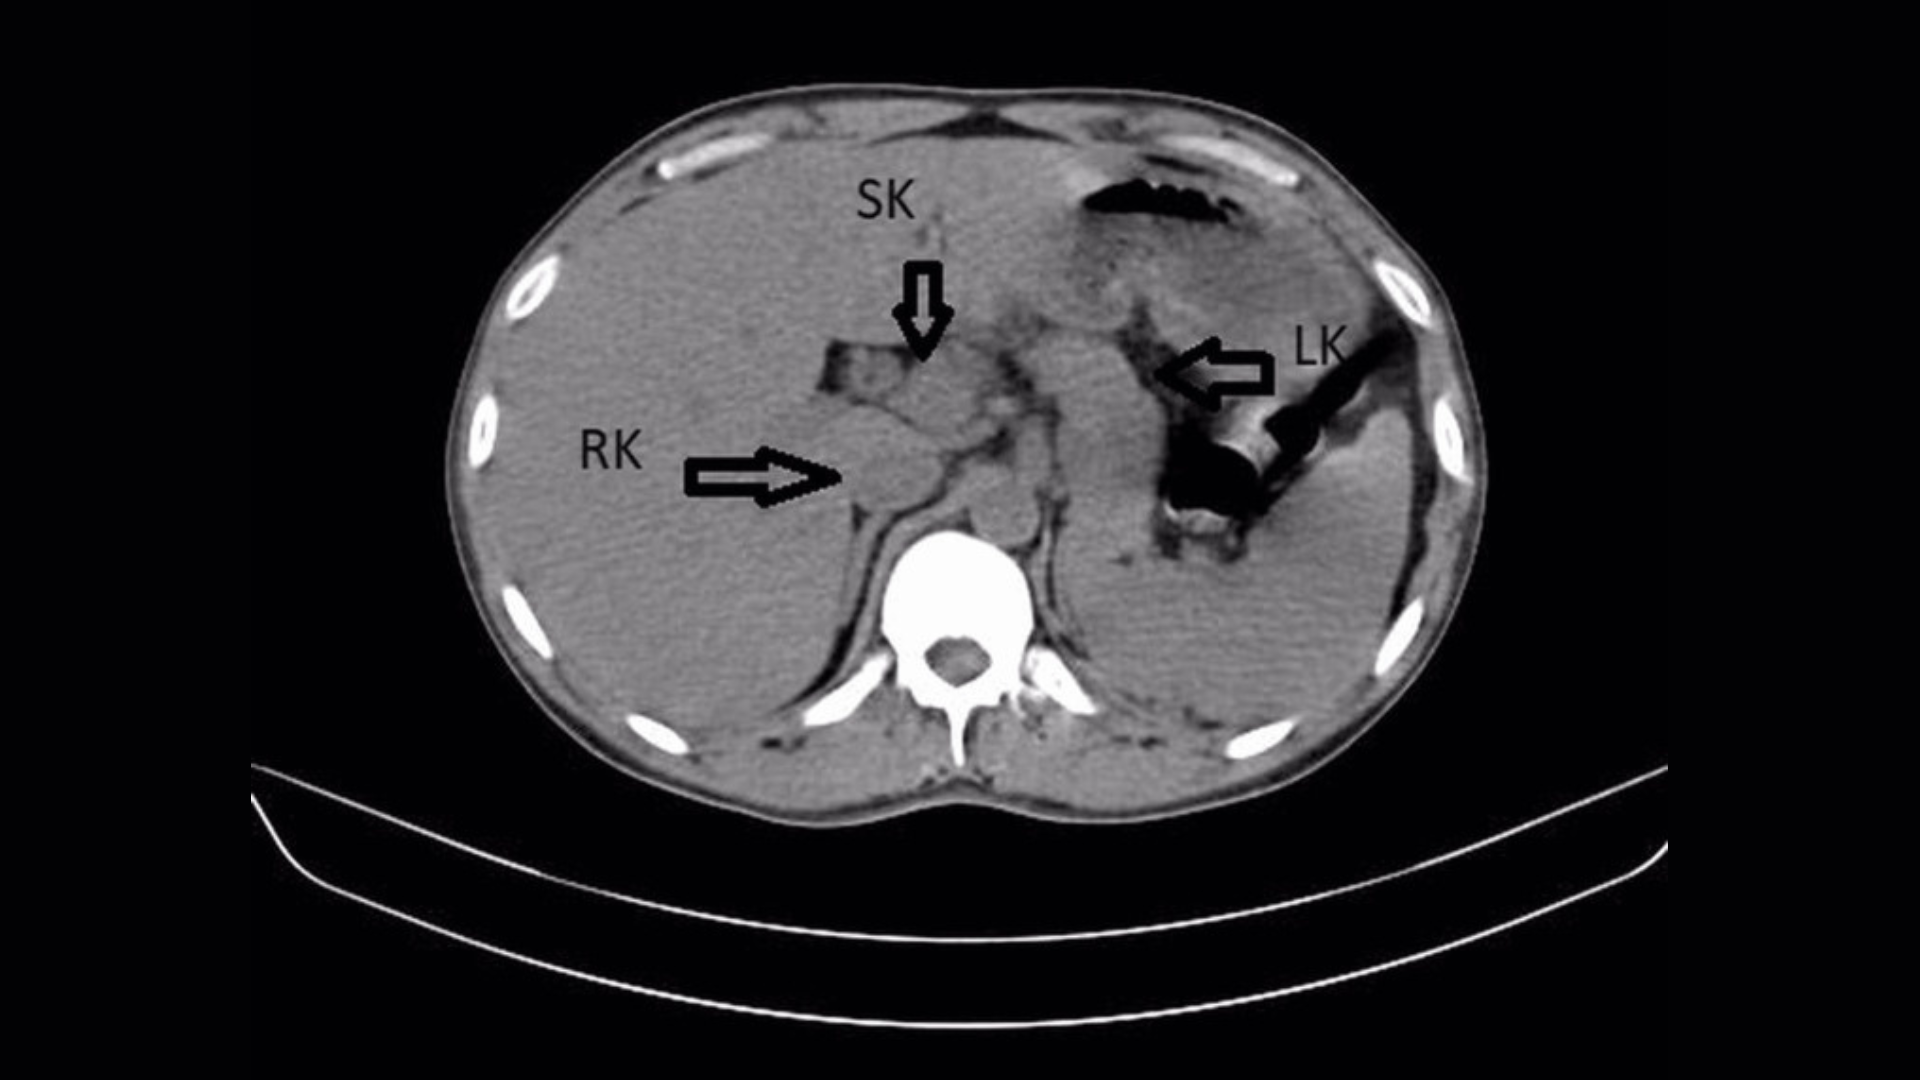

A CT scan revealed not two kidneys, but three. The scan clearly showed the locations of the patient’s right kidney, left kidney, and a third “supernumerary” kidney — a medically documented but extraordinarily uncommon anatomical variation.

| Kidneys identified on scan | Right kidney, left kidney, supernumerary kidney |

The case was published in the medical journal Cureus in 2022, authored by Nimkar et al., and included CT scan imaging showing all three kidneys.